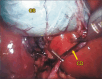

Results: Of the 375 patients, 26 (6.9%) had laparoscopic anatomical variations, of whom 19 (73.1%) had vascular variations and seven (26.9%) had ductal variations. The anatomical variations included the following: double cystic artery of separated origin, seven cases (26.9%); Moynihan's hump, six (23.1%); double cystic artery of single origin, four (15.4%); thin long cystic duct, four (15.4%); subvesical duct, three (11.5%); and cystic artery hocking the cystic duct, two (7.7%).